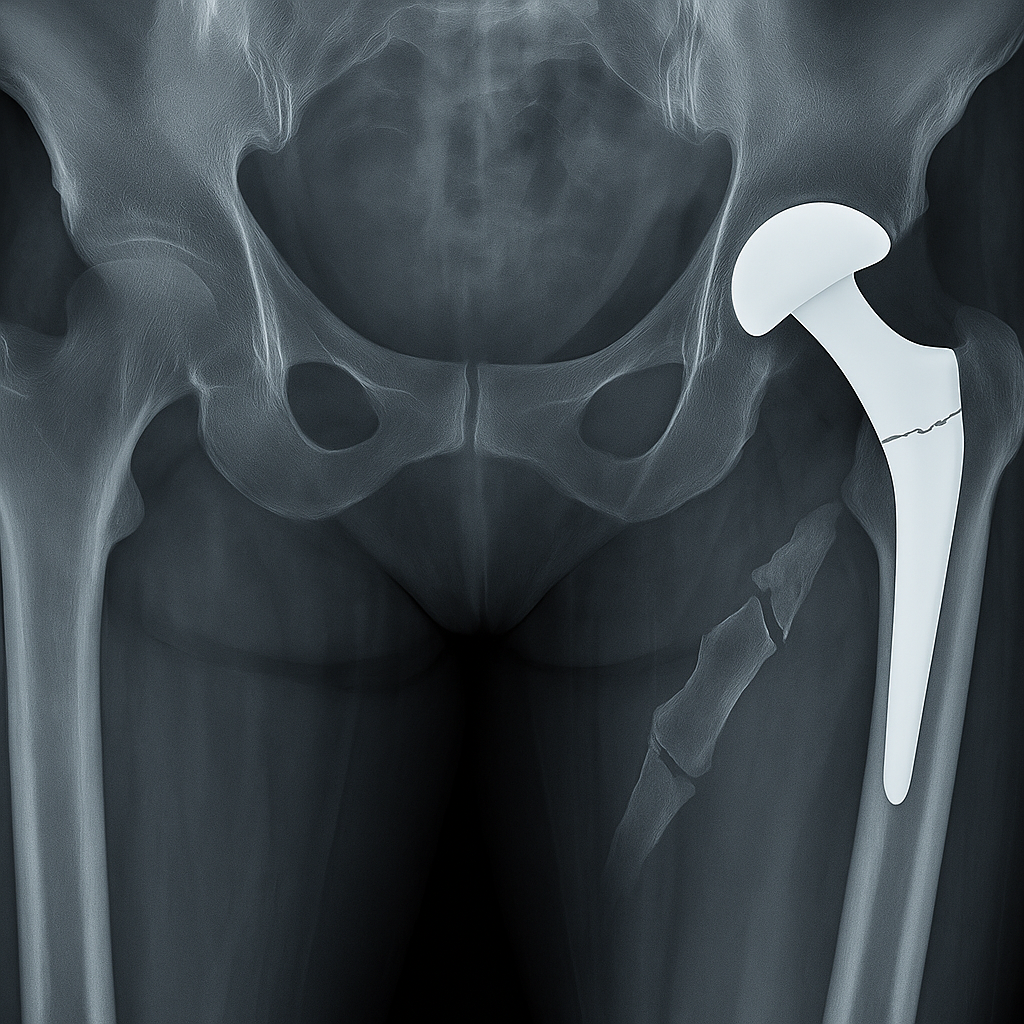

Zimmer Biomet CPT®

Hip System

If you or a loved one received a Zimmer Biomet CPT® Hip System implant, you may face a significantly higher risk of serious injury, including painful thigh bone fractures. Recent warnings from the FDA and medical researchers have raised major concerns about the safety of this device, and patients harmed by the CPT Hip System may now be eligible for compensation.

In July 2024, Zimmer Biomet issued a recall related to the instructions for its CPT Hip System Femoral Stem. New research revealed that patients implanted with this device are more than twice as likely to suffer a thigh bone fracture compared to patients with other hip implants.

Despite announcing plans to discontinue the device by December 2024, Zimmer Biomet has continued to allow the CPT Hip System to be used in surgeries — putting more patients at risk.

In response, the FDA issued a public safety alert in September 2024, warning surgeons and patients about the dangers associated with this device.